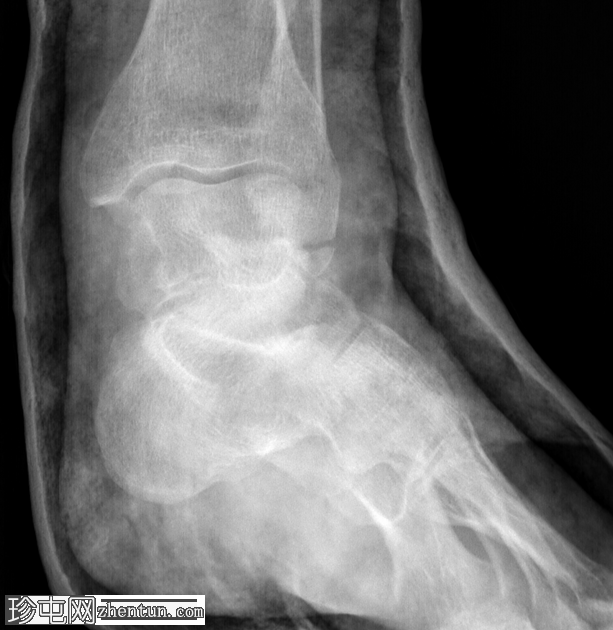

X光片

正面

胫腓联合下方外踝完全横向骨折,石膏固定复位。

左脚韦伯A型外踝骨折石膏固定复位后的随访X光片。